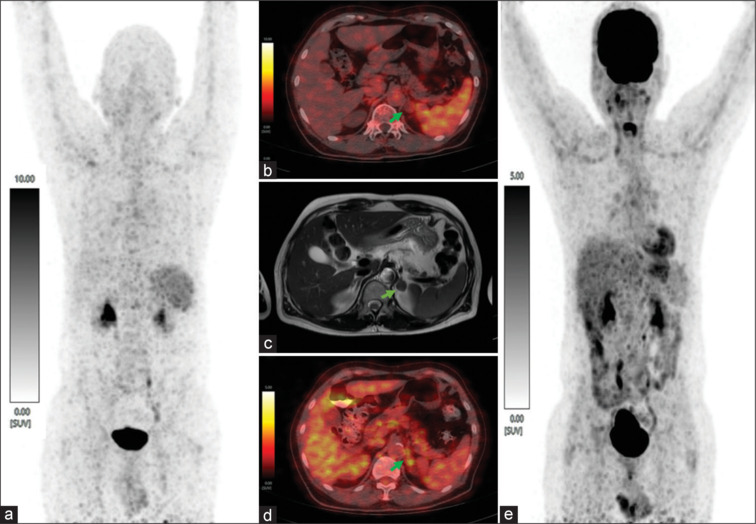

A 65-year-old male with systemic hypertension, progressively rising aldosterone levels, low plasma renin activity, contrast Magnetic resonance imaging (MRI) described left adrenal lesion isointense to liver parenchyma on T2-weighted images and other features suggestive of left adrenal incidentaloma underwent 68Ga-Pentixafor Positron emission tomography-computed tomography (PET/CT), which unexpectedly did not show tracer uptake in the known left adrenal adenoma. However, the said nodule showed significant focal tracer uptake on F-18 Fluorodeoxyglucose (FDG)-PET/CT that was done within 2 weeks of 68Ga-Pentixafor PET/CT study. This unusual finding, which has hitherto been unreported in known patients of primary aldosteronism needs further exploration to determine its clinical significance.

65岁男性,全身性高血压,醛固酮水平逐渐升高,血浆肾素活性低,磁共振成像(MRI)在t2加权图像上描述了左肾上腺病变与肝实质等强度,以及其他提示左肾上腺偶发瘤的特征,进行了68ga - pentxafor正电子发射断层扫描-计算机断层扫描(PET/CT),出乎意料的是,在已知的左肾上腺腺瘤中未显示示踪剂摄取。然而,在68Ga-Pentixafor PET/CT研究的2周内,该结节在F-18氟脱氧葡萄糖(FDG)-PET/CT上显示出明显的局灶示踪剂摄取。这一不寻常的发现,迄今未在已知的原发性醛固酮增多症患者中报道,需要进一步探索以确定其临床意义。